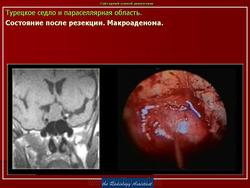

ГМ. Аденома гипофиза 1. +

Аденома гипофиза.